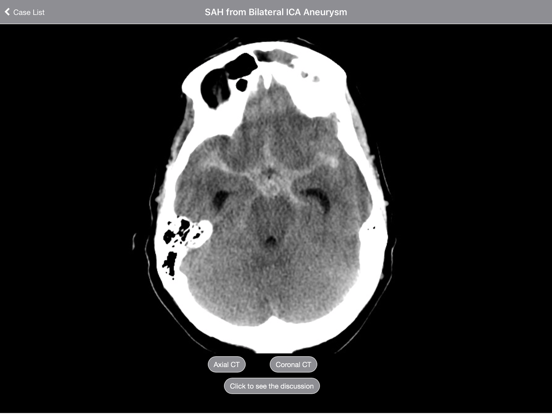

The purpose of this tutorial is to introduce you to the most common basic pathologies seen on a head CT scan: stroke, mass, and bleed. After viewing these 63 cases you will have seen multiple examples of each entity and should be familiar with the varied appearance of each.

Each case is presented as a complete CT scan that you can scroll through as if at a PACS workstation. Each exam is discussed in an interactive format. Important findings are highlighted with arrows, circles, and colorful schematics. Multiple examples of each type of pathology are presented so you can learn by repetition. Varied appearances of similar diagnoses are included. The first case in each section has a comprehensive description of the featured disorder. Subsequent cases utilize shorter descriptions and focus on the pertinent findings.

Entire cases are presented as scrollable stacks. Extensive, interactive discussions accompany each case and include labeled images that highlight pathologies and relevant findings. Rather than use static images to teach specific diagnoses, Radiology 2.0 uses stacks of images to actually teach the reader how to approach and interpret scans.